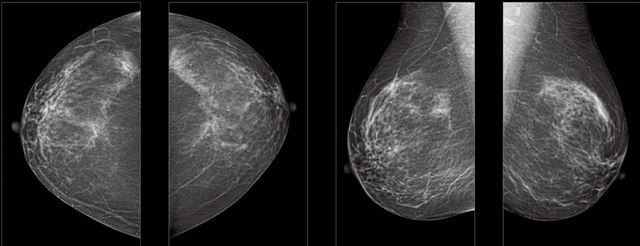

首先不同年齡階段的乳腺篩查頻次種類不一樣。青春期女性第二性征明顯發(fā)育開始,每個(gè)月進(jìn)行自我乳腺檢查。20-30歲的女性就不推薦進(jìn)行乳腺檢查,因?yàn)槟贻p女性的乳腺組織非常緊急。鉬靶X光線等檢查的射線不能辨別腫塊跟腺體。身體就白吸收了輻射,影響了身體健康。每個(gè)月自檢一次就是在洗澡時(shí)候,對(duì)著鏡子看看乳房外觀正常,皮膚潰爛、腫塊、顏色改變、再摸一下有沒(méi)小疙瘩。乳腺高危人群,特別是有乳腺CA遺傳傾向的女性,乳腺導(dǎo)管跟小葉不典型增生,原位癌。30歲前有乳房放療的女性。乳腺癌篩查可以把年齡提前到40歲前。40到70歲的女性可以在適合的機(jī)會(huì)篩查。

采用影像檢查技術(shù)來(lái)發(fā)現(xiàn)疑似特定病檢查跟人群的普查。一到兩年進(jìn)行一次X光線的乳腺檢查。記過(guò)是C或者D型,可以加上B超協(xié)同。還可以一年一次核磁共振MRI檢查。70歲以上的女性認(rèn)為絕經(jīng)的女性是比較安全的。實(shí)際上也有乳腺癌的風(fēng)險(xiǎn)。65歲以上風(fēng)險(xiǎn)也很大。也是需要進(jìn)行機(jī)會(huì)性篩查。